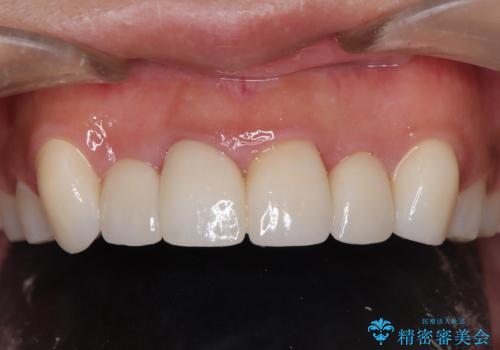

最終的なかぶせものを入れる前に、ホワイトニングもして歯の色を明るくしてからその色に合わせて新しいかぶせものを用意しました。

最終的なかぶせものを入れる前に、PMTCやホワイトニングをしてきれいに、かつ白くなってからかぶせものを作成すると、より仕上がりに対しての満足感がアップすると思います。